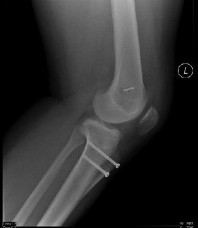

Question 14:

A 23-year-old collegiate basketball player sustains a fracture of the fifth metatarsal at the metaphyseal-diaphyseal junction (Jones fracture). He demands the quickest safe return to play. What is the current standard of care for a competitive athlete with an acute Jones fracture?

Correct Answer: Percutaneous intramedullary screw fixation

Explanation:

Acute Jones fractures (Zone II) in high-level competitive athletes are best treated with intramedullary screw fixation. This approach significantly decreases the time to clinical and radiographic union, decreases the nonunion rate, and allows for a much earlier return to play compared to conservative management.